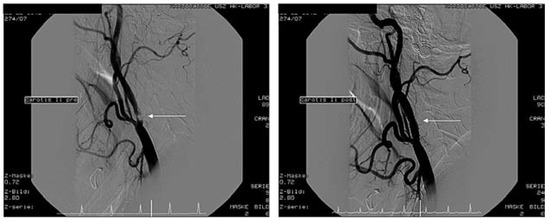

Nichtkoronare Eingriffe—Neue Horizonte in der Kardiologie und Herz-Gefäss-Chirurgie

by Thomas F. Lüscher, Lukas Altwegg and M. Roffi

Cardiovasc. Med. 2007, 10(7), 229; https://doi.org/10.4414/cvm.2007.01259 - 24 Aug 2007

Die koronare Herzkrankheit ist das mit Abstand bedeutendste Krankheitsbild der kardiovaskulären Medizin [...] Full article

Show Figures

Figure 1